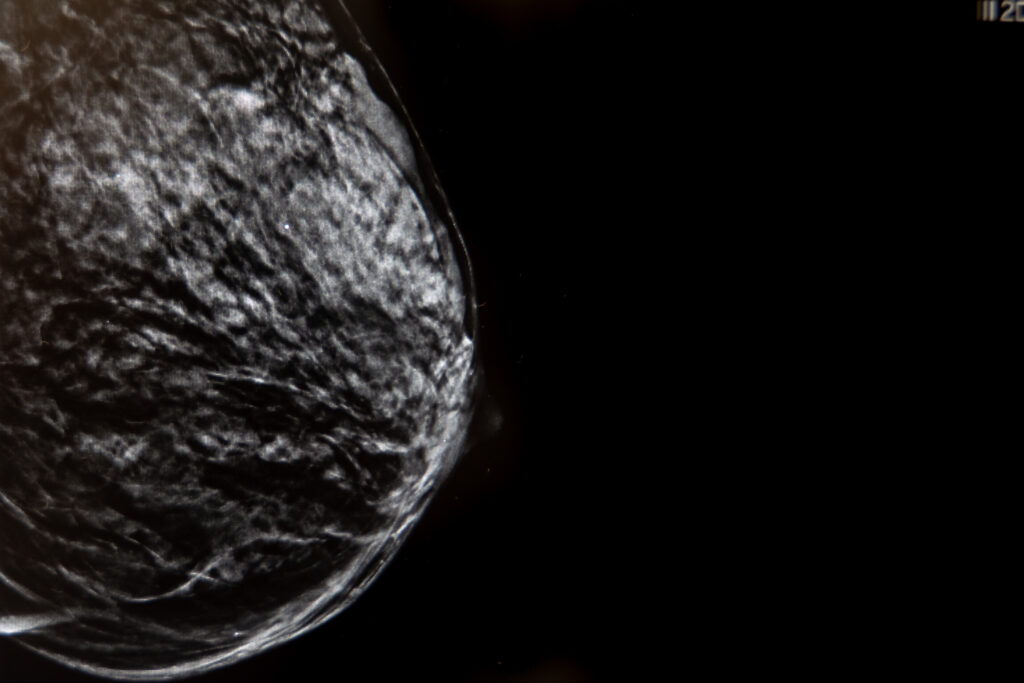

La mamografía con tomosíntesis, también conocida como mamografía 3D, es una técnica avanzada de imagen mamaria que utiliza rayos X de baja dosis para crear una imagen tridimensional de la mama. A diferencia de la mamografía tradicional, que proporciona una imagen bidimensional, la tomosíntesis captura múltiples imágenes desde diferentes ángulos, permitiendo una visualización más detallada del tejido mamario.

- Imágenes 3D: proporciona una visualización tridimensional de la mama, permitiendo una mejor detección de lesiones.